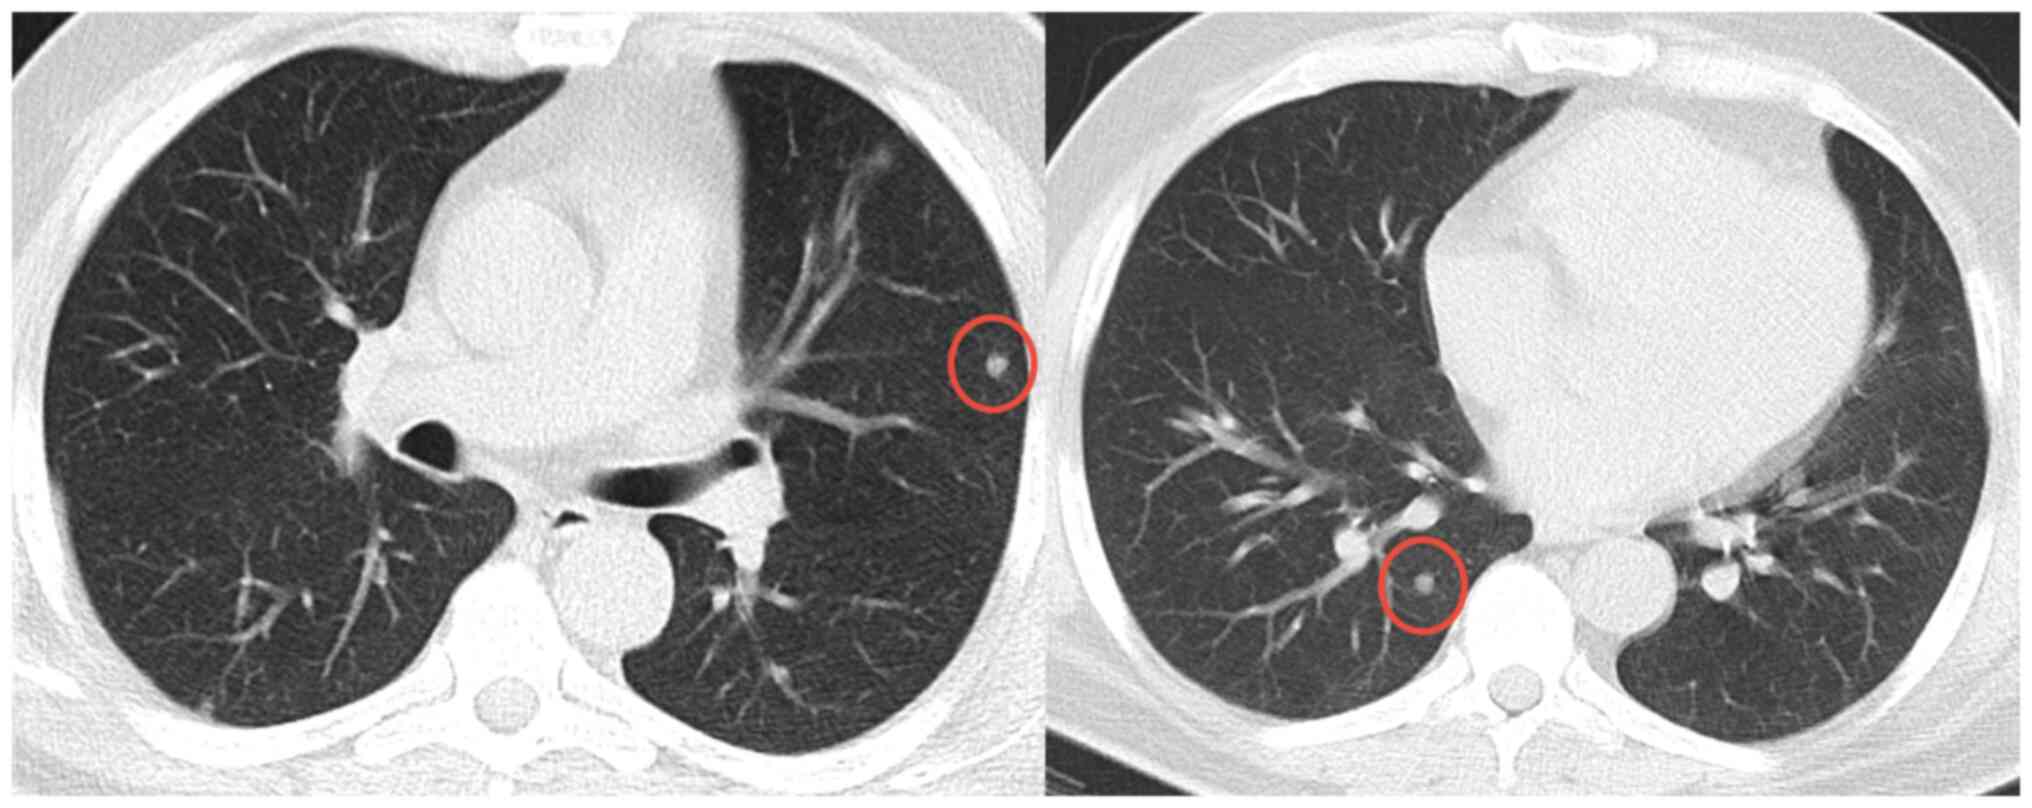

Case 3

In January 2019, an 11-year-old female was referred to the Masaryk Memorial Cancer Institute Sarcoma Center with a 2-month history of pain in the right foot. MRI scans showed a 3 cm thickening of the bone in the V. metatarsal diaphysis (Fig. 11). The histopathology report showed an intermediate-grade periosteal osteosarcoma (Fig. 12). The patient had no lymph node involvement or metastases. The Musculoskeletal Tumor Committee recommended en bloc resection with bone allograft reconstruction using a plate. The final histopathology report confirmed the initial findings from the biopsy (Fig. 13). After 2 years, a follow-up plain radiographs showed ossification on the allograft surface (Fig. 14), leading to a biopsy to check for any signs of local recurrence. The biopsy results showed no evidence of malignancy (Fig. 15). At the time of writing, the patient completed 5 years of follow-up appointments with no signs of disease recurrence.

Figure 11.

Case 3. (A) MRI showing a periosteal osteosarcoma of the fifth metatarsal. (B) Postoperative radiographic imaging following complete resection and reconstruction with a bone allograft and plate fixation.